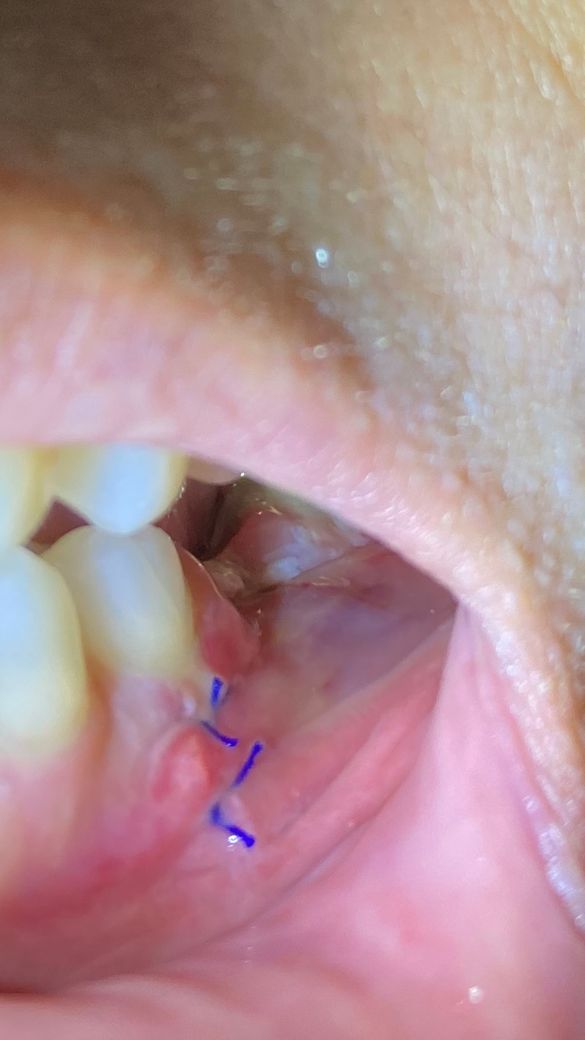

뼈이식 임플란트 식립했는데 잘 아물고 있는건가요?

임플란트는 지난 3월3일에 했고 4일차 입니다.

잇몸절개하고 뼈이식 임플란트 식립을 했습니다.

사진상으로 보면 잘 아물고 잇는거 같습니다. 헥사메딘은 5일이상 사용하시면안됩니다. 장기간 사용하면 착색이 될수 있습니다.

현재 사진상으로는 잘아물고 있는 것으로 보입니다.

다만 노란색 액체들이 고름과 비슷해보여서 해당 부분은 확인이 필요할 것 같습니다. 통증이 가시지 않을수는 있지만 우선 치과에 한번 내원해보시는 것이 좋겠습니다.

사진을 봤을 경우에는 잇몸이 아물고 있는것으로 보입니다.

사진상 문제는 없어보입니다